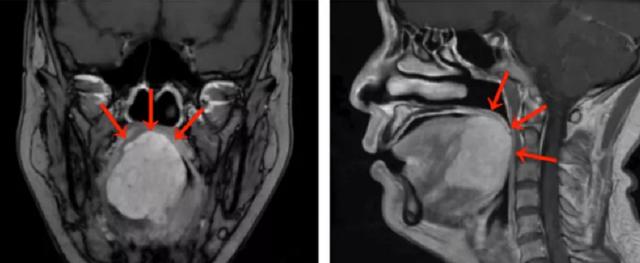

“刘女士的舌根部肿物达到5厘米,几乎占据整个舌根部并向口咽腔突出。”医生表示,MRI检查提示舌根肿块巨大,范围约47毫米×46毫米×45毫米,向前侵犯部分舌体,向下侵犯部分口底肌群。活检病理诊断考虑为舌根腺样囊性癌。